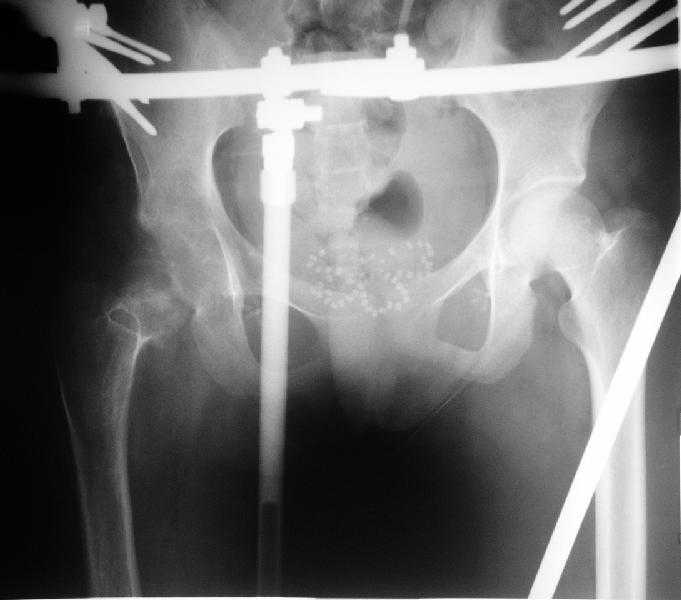

Поступила к нам в отделение. В отделении первым этапом был наложен аппарат внешней фиксации для низведения бедра. 30.09.08 интрамедуллярный стержень удален. Вторым этапом планируется эндопротезирование. В настоящее время у больной имеется контрактура коленного сустава, с амплитудой движений в пределах 30 градусов., и выраженный остеопороз вертлужной впадины и проксимального отдела бедра. Больныя пердвигается самостоятельно с опорой на здоровую ногу и костыли.

Какие проблемы при эндопротезиовании в этих условиях ожидать, и как с ними бороться? Еще и диафиз сросся не очень крепко, опасаемся, как бы не сломать. Очень выражен местный остеопороз, может быть, сделать все-таки цементный протез? Хотя 18 лет всего. Спасибо.